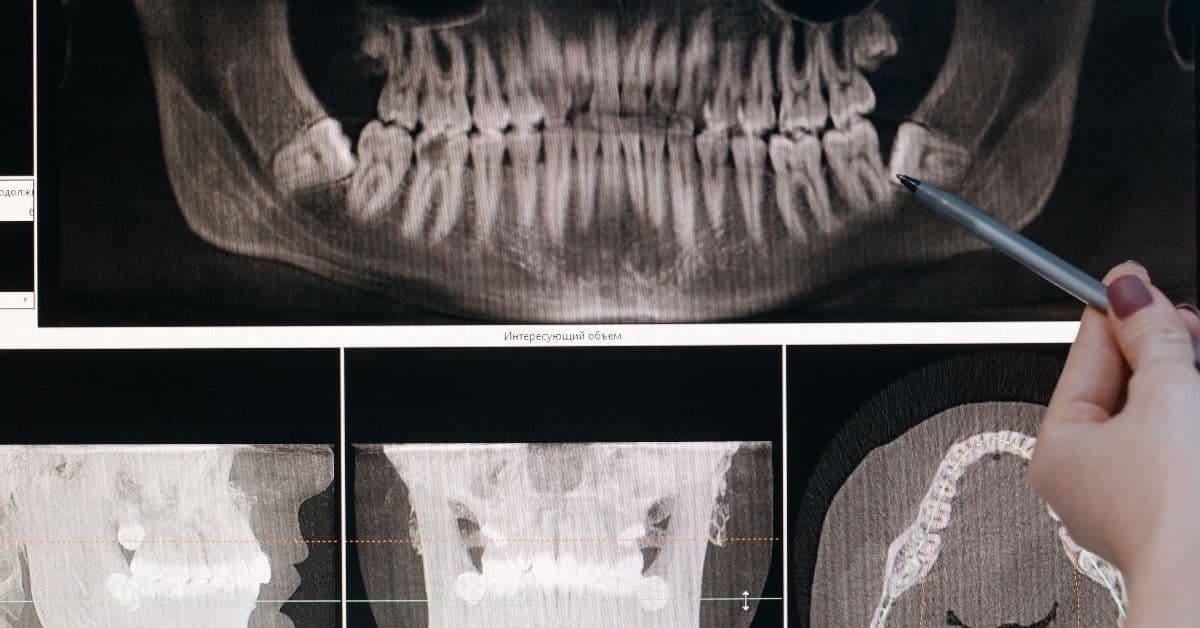

Computer guided implantology

This type of implantology allows dental implants to be placed with more precision, in less time and with a less invasive operation thanks to the use of software and three-dimensional models of the patient's mouth with which to predict possible complications and establish the stages of the operation.